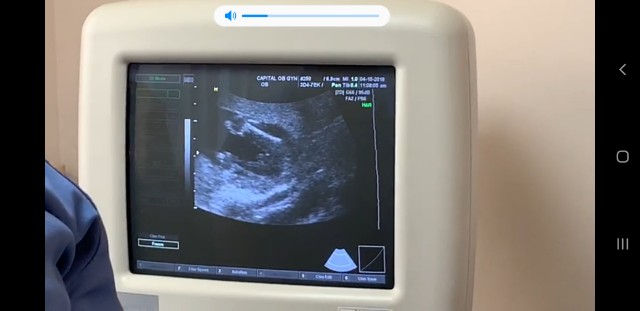

17 weeks &1 day ... it's a girl or boy??? My sex reveal is on Friday but I see a boy in this picture